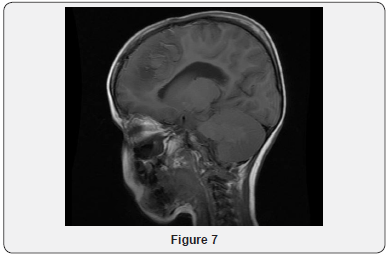

Echocardiogram Holter monitor and Eye examination all were normal. The patient underwent muscle biopsy which showed mild lipid myopathy with type 2 muscle fiber atrophy, but with no morphological evidence of mitochondrial disease. A stat CT brain showed hemorrhagic infarction and some fresh bleeding in subarachnoid space (not older than 3 days), possibly on the basis of ischemic lesions, considering the further hypodense lesions in the parasagittal area on bi-occipital and parieto-occipital regions, more extended on the left side (Figure 4). The neurosurgery team was notified, but it was determined that the patient has poor prognosis and is not candidate for surgery. Gradually, the patient developed respiratory distress and was transferred to the intensive care unit and required mechanical ventilation. He was monitored continuously by EEG. At that time, he showed subclinical seizures originating from the posterior head region, right side more than left. A burst suppression pattern was established, but during the burst period he was having multifocal spikes and polyspikes. Brain MRI showed massive hemorrhagic infarction of non-vascular distribution pattern involving the posterior occipito-parietal, region with brain stem area and cerebellum (Figures 5-9) and a lesion extending to the temporo-parietal region (Figures 5,7). Cerebral angiography showed multiple territorial hemorrhagic infarctions, with no blood entering intracranially in a case of massive intracranial edema, suggesting brain death (Figure 10). Using homozygosity mapping followed by whole exome sequencing, we identified a homozygous mutation of APOA1BP that caused lethal infantile leukoencephalopathy. The patient continued to deteriorate, then died at the age of four years.